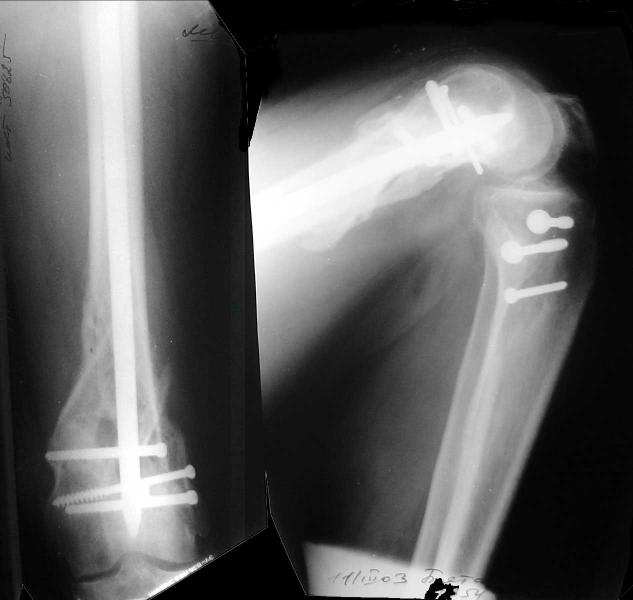

And why LISS is superior here than nail?

Look what we would have done.

I would not say that the LISS is superior to the nail. If I would, I had not post original mail. I wanted to generate discussion. Your option is a very viable one. I feel a little bit shaky the distal femur, but it is just gut feeling no science behind it. Any way nice fixation, congarts!

ZB> Any way nice fixation, congarts!

Same to you ;-))

I presented the series at EuroTrauma in May. The "Distal Femur" section of the meeting was very interesting.